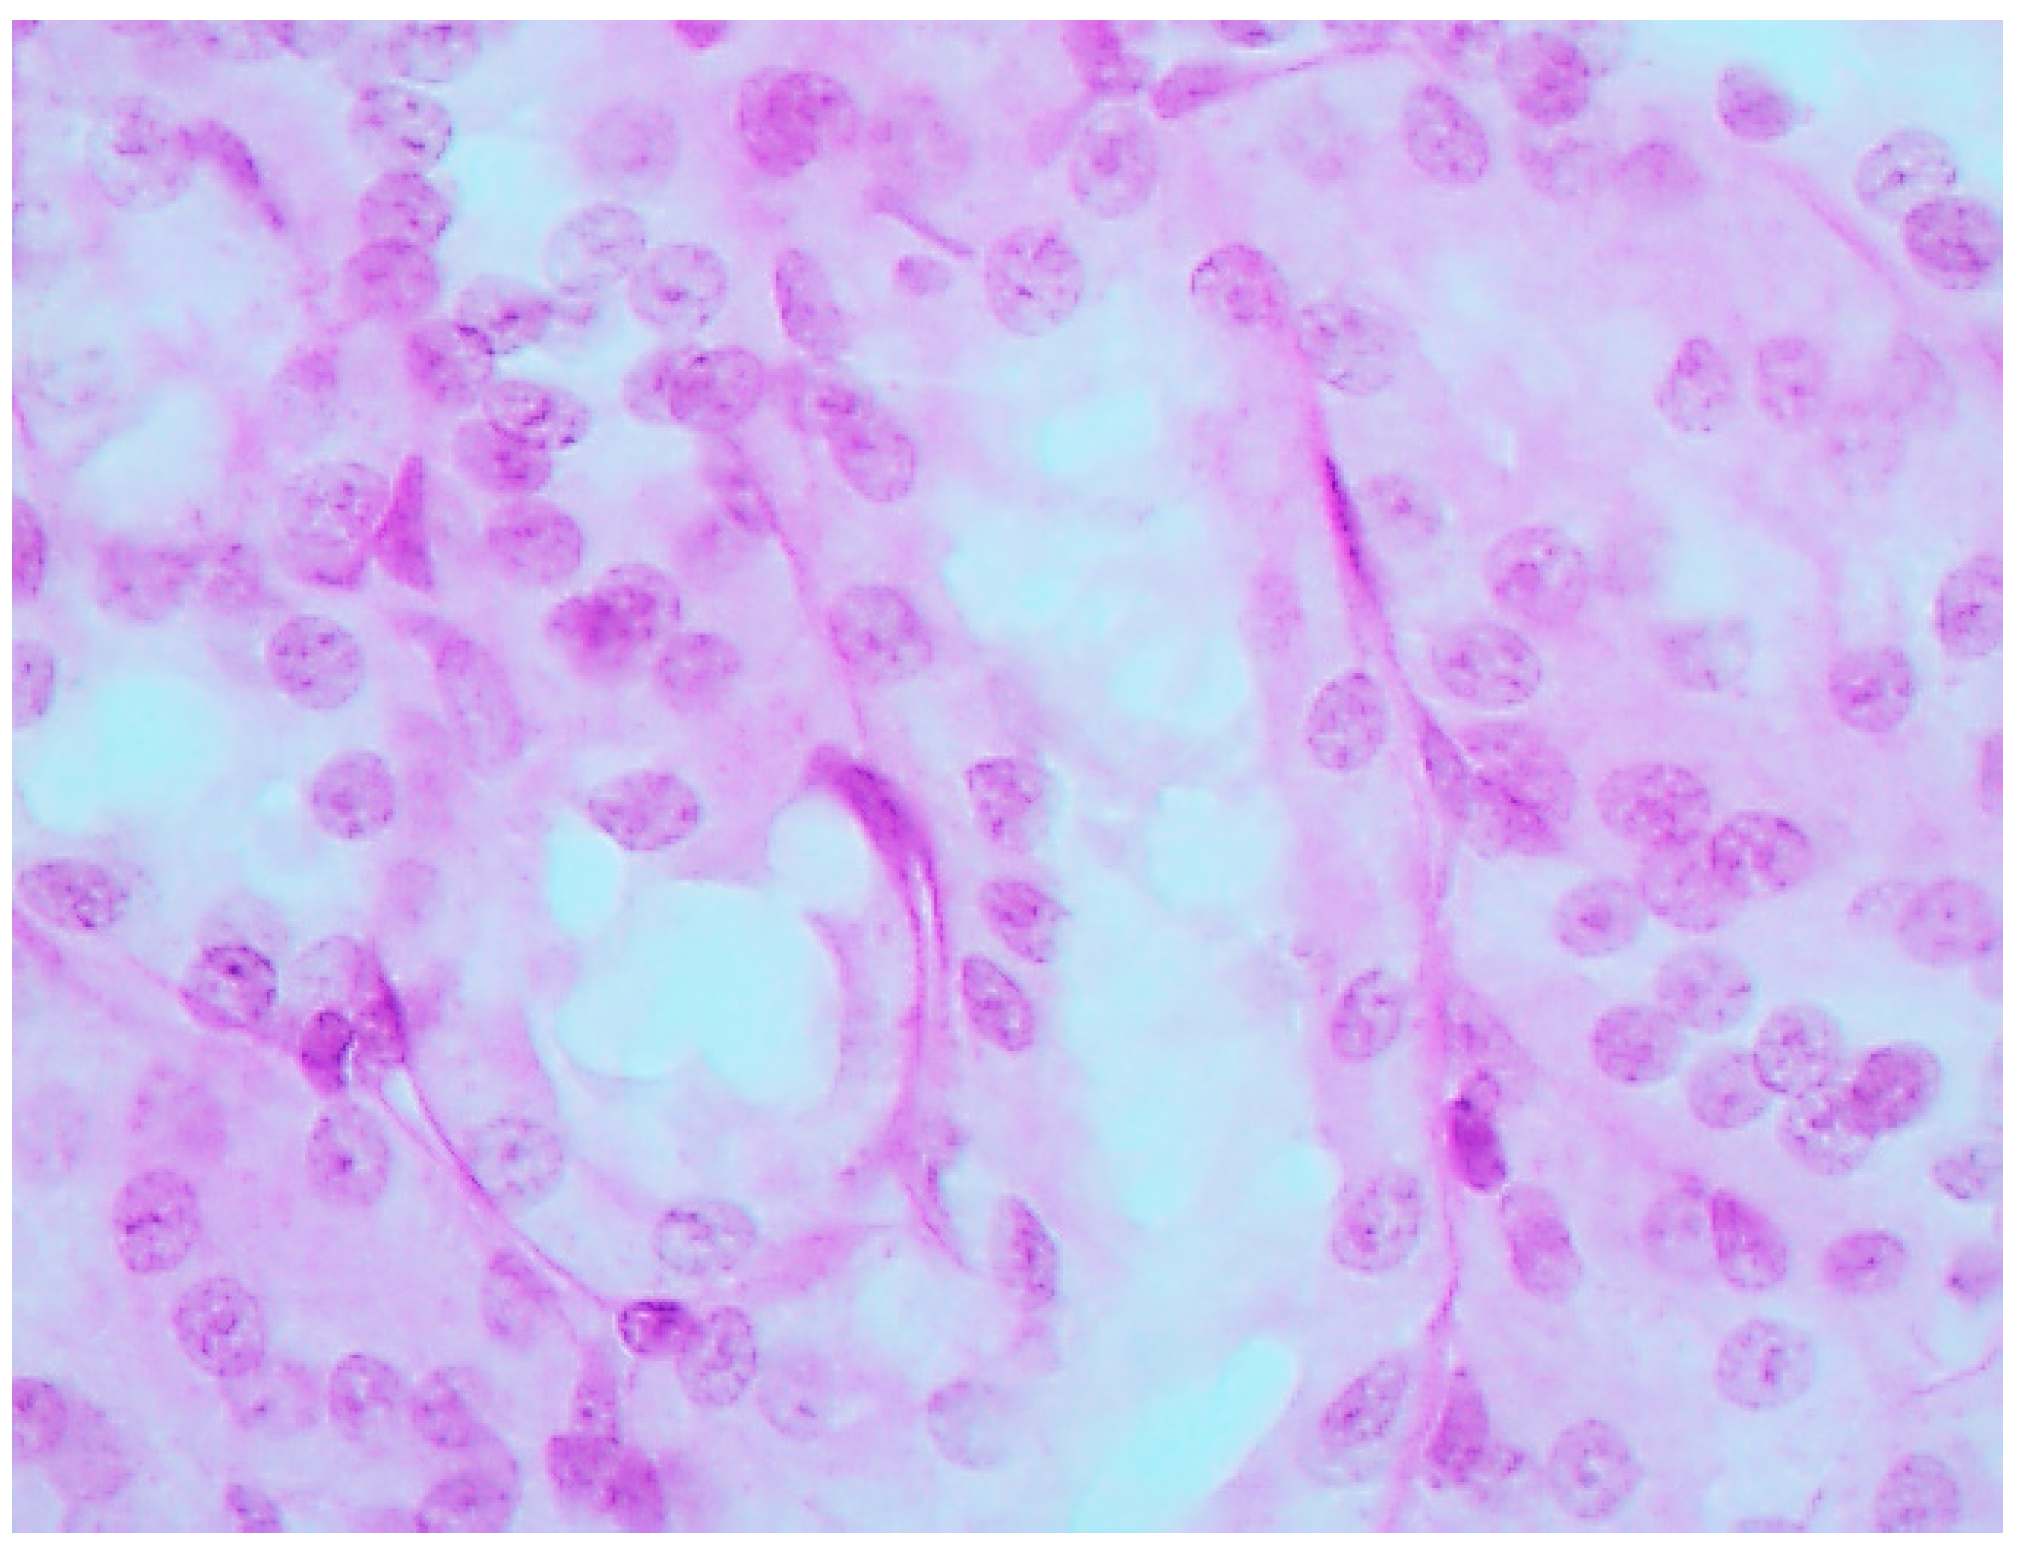

The histological picture (Figure 2, Figure 3 and Figure 4) and morphometric characteristic (Table 4) of the epithelium in the proximal convoluted tubules provide evidence of marked damage, which is a little more marked in response to NiO-NPs and, particularly, Mn3O4-NPs + NiO-NPs, than to Mn3O4-NPs alone, but is absent for the same combined intoxication with the background administration of the BPC.

Figure 3. Kidney of a rat exposed to nanoparticles of NiO and Mn3O4 together. Marked degenerative and necrobiotic changes of tubular epithelial cells up to their disappearance; partial destruction of the brush border. PAS stain, magnification ×400.

Ijms 16 22555 g003